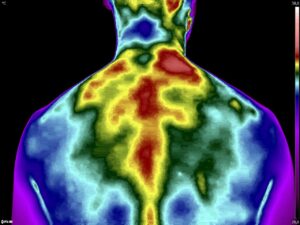

Como no caso dos termogramas abaixo de um paciente do sexo masculino, 44 anos, sem comorbidades e que apresentou dor em cervical. Foi realizado uma Análise Termofuncional e detectado alterações térmicas condizentes com o relato de dor.

Com estes achados foi possível determinar a cadeia postural que acometia o paciente, determinando o seu tratamento.

Somente com o conhecimento integral do Método de Termografia Infravermelha é possível detectar alterações e associá-las a uma disfunção.